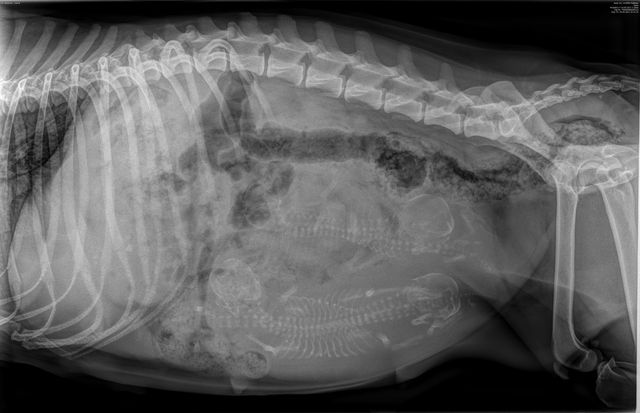

As with every litter, we went for an x-ray a week before the birth date. And we were able to take the first family photo. We are expecting 4 little ones from Diana & Spike. We are very excited and are now waiting together with the proud mom for the happy event.

Röntgenbild vom F-Wurf